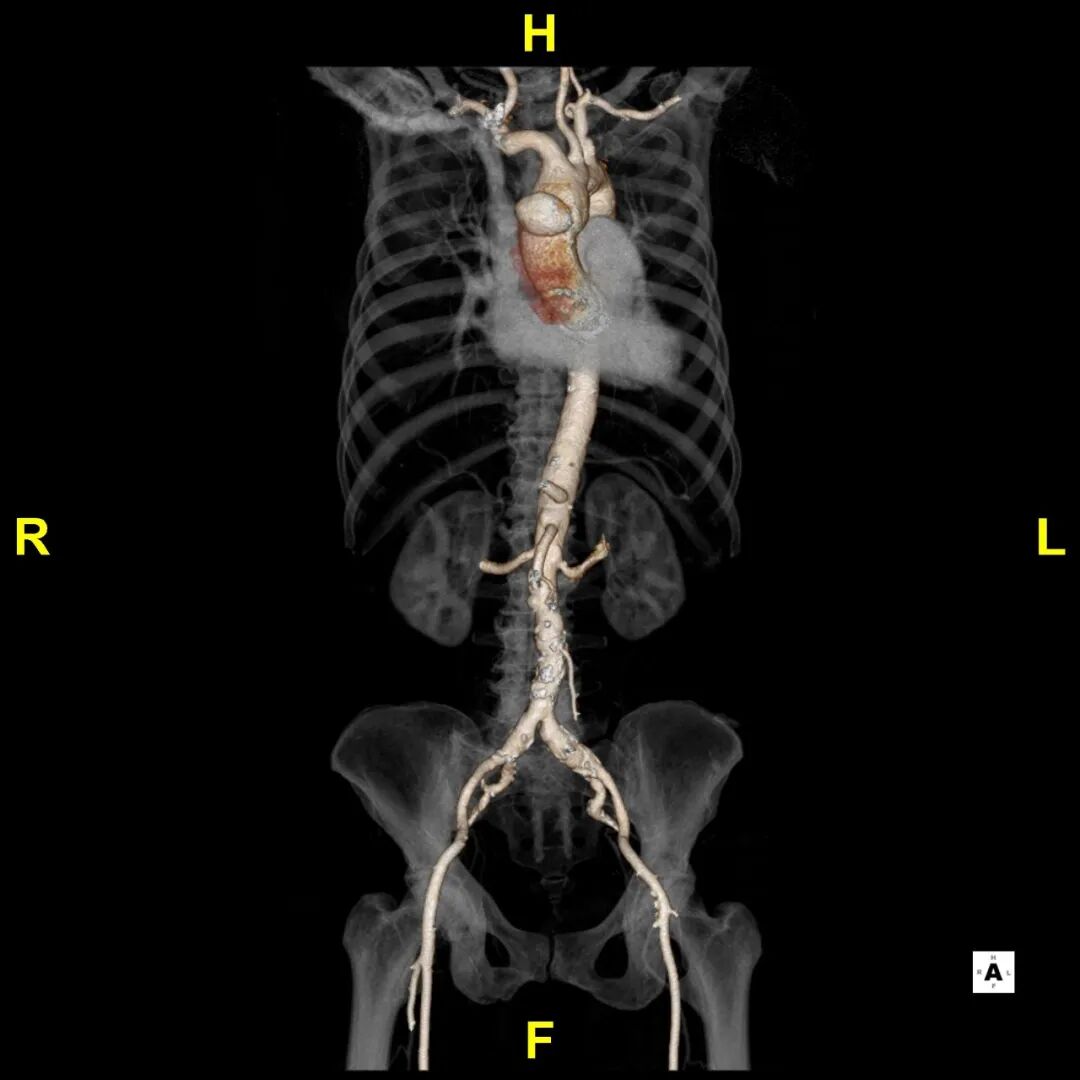

术后随访

患者出院前进行CTA复查,可见溃疡隔绝完全,弓上分支血管及冠状动脉通畅。

术后3D重建